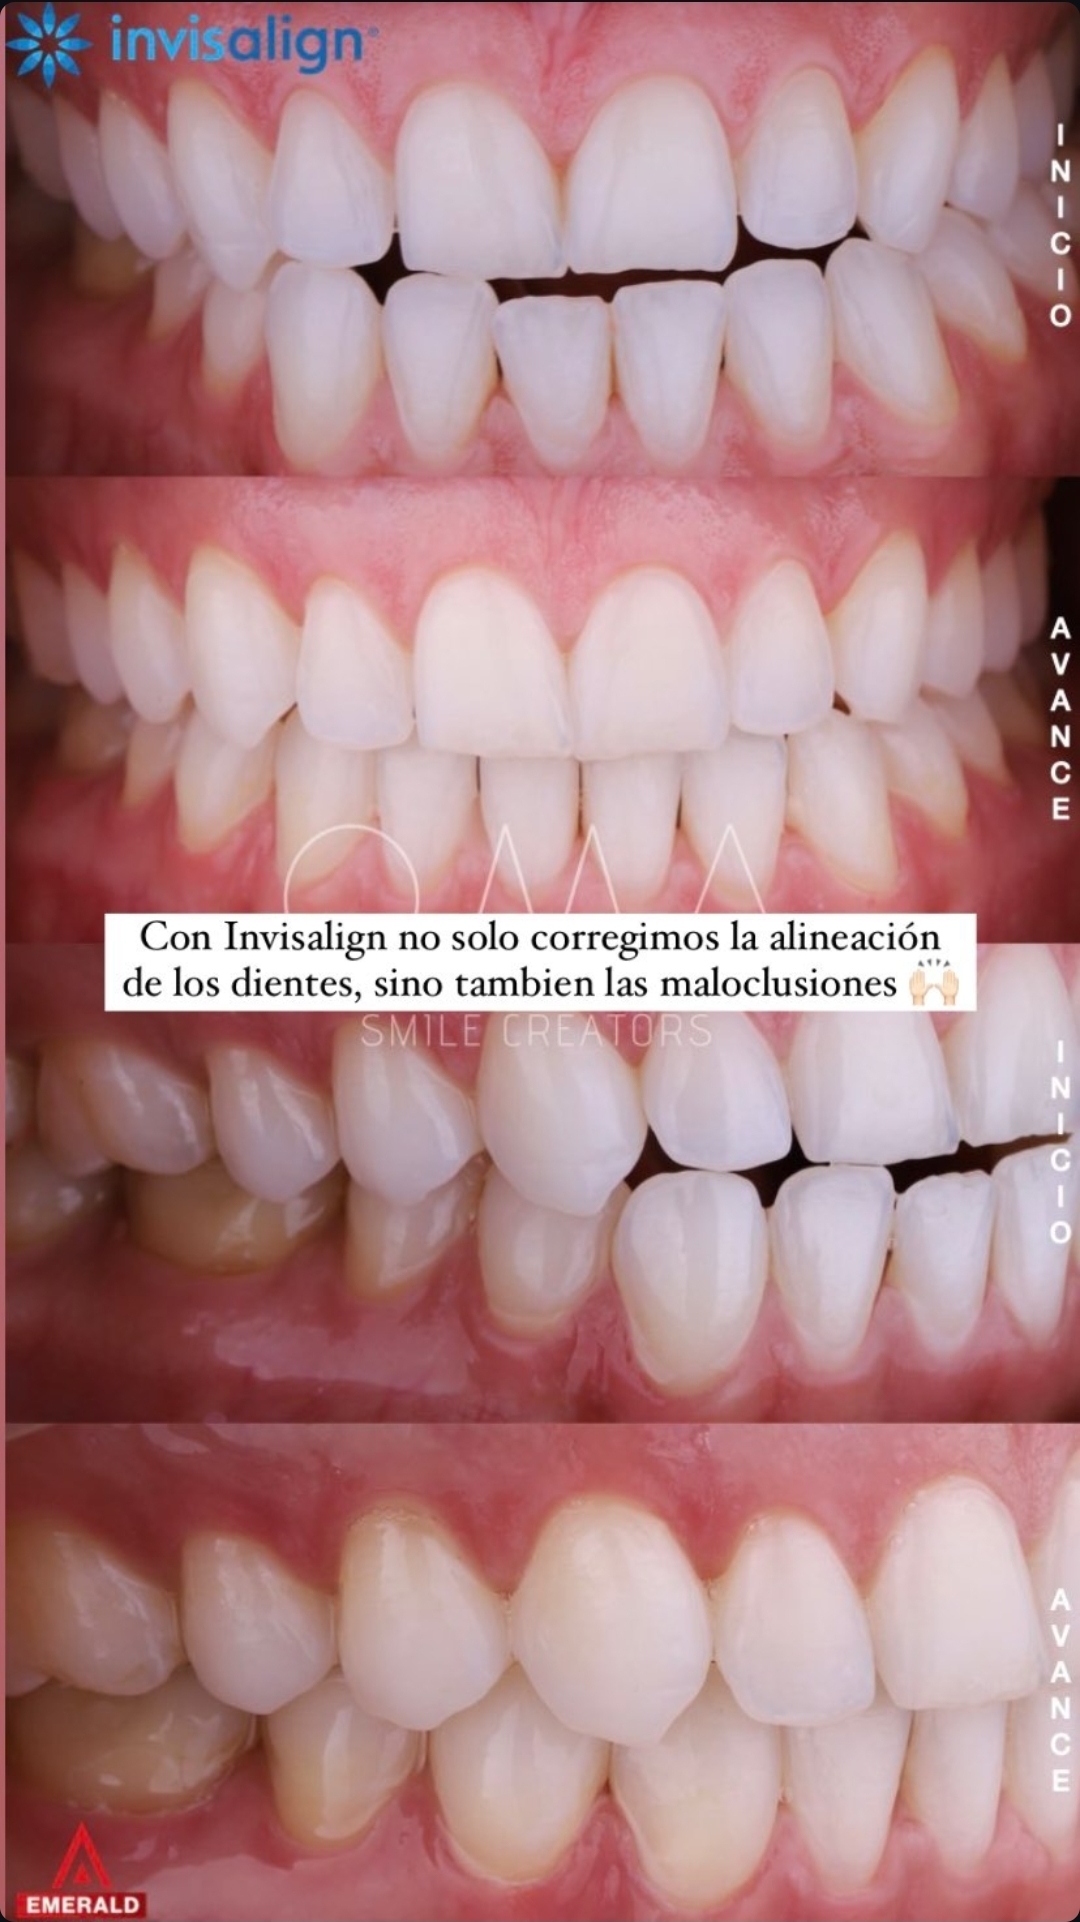

Alineadores invisibles, removibles. Corrección de alineación y maloclusiones con simulación 3D previa.

Alineadores invisibles, removibles. Corrección de alineación y maloclusiones con simulación 3D previa.